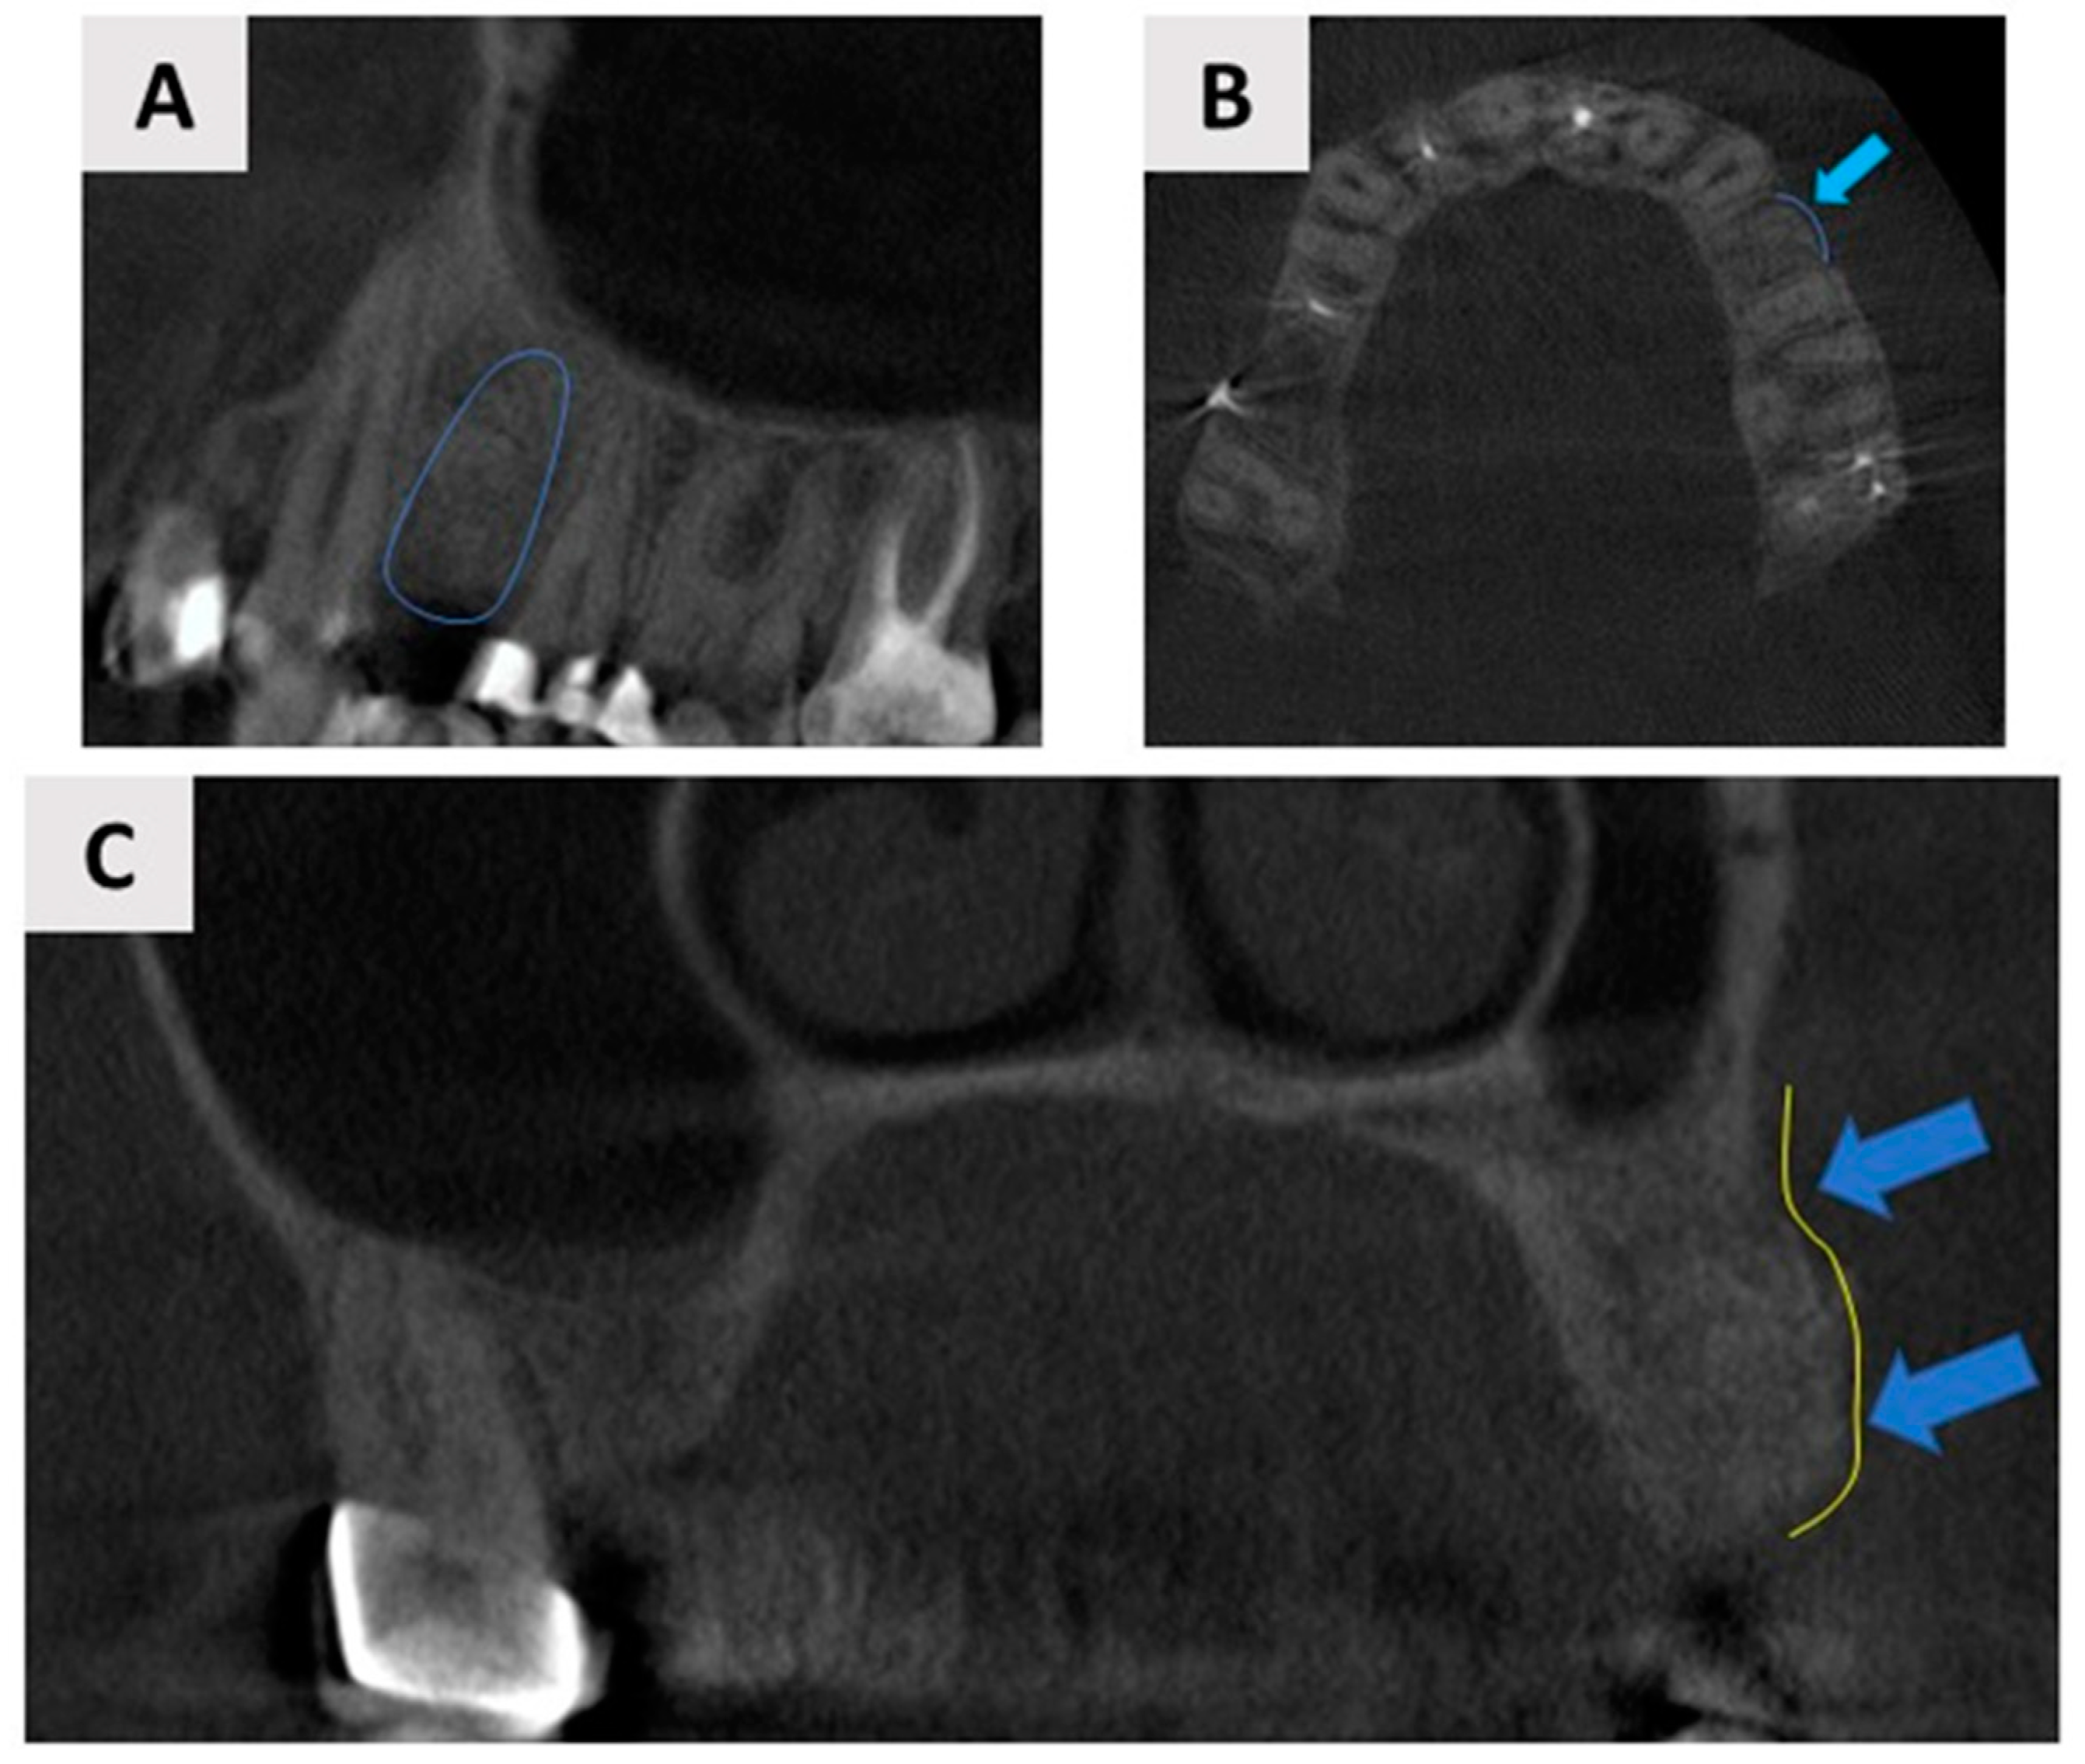

2.1. Patient Description, Case History, and Ethical Considerations

2.2. Planning the Magnesium Membrane Shield Technique Surgery and Materials Used

2.4. Healing Phase and Dental Implant Placement Planning

2.5. Dental Implant Placement and Bone Biopsy Harvesting